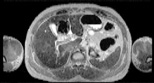

Visible Human male: Sectio transversalis 1540

CT

NMR

Pd                          / T2 \                         T1